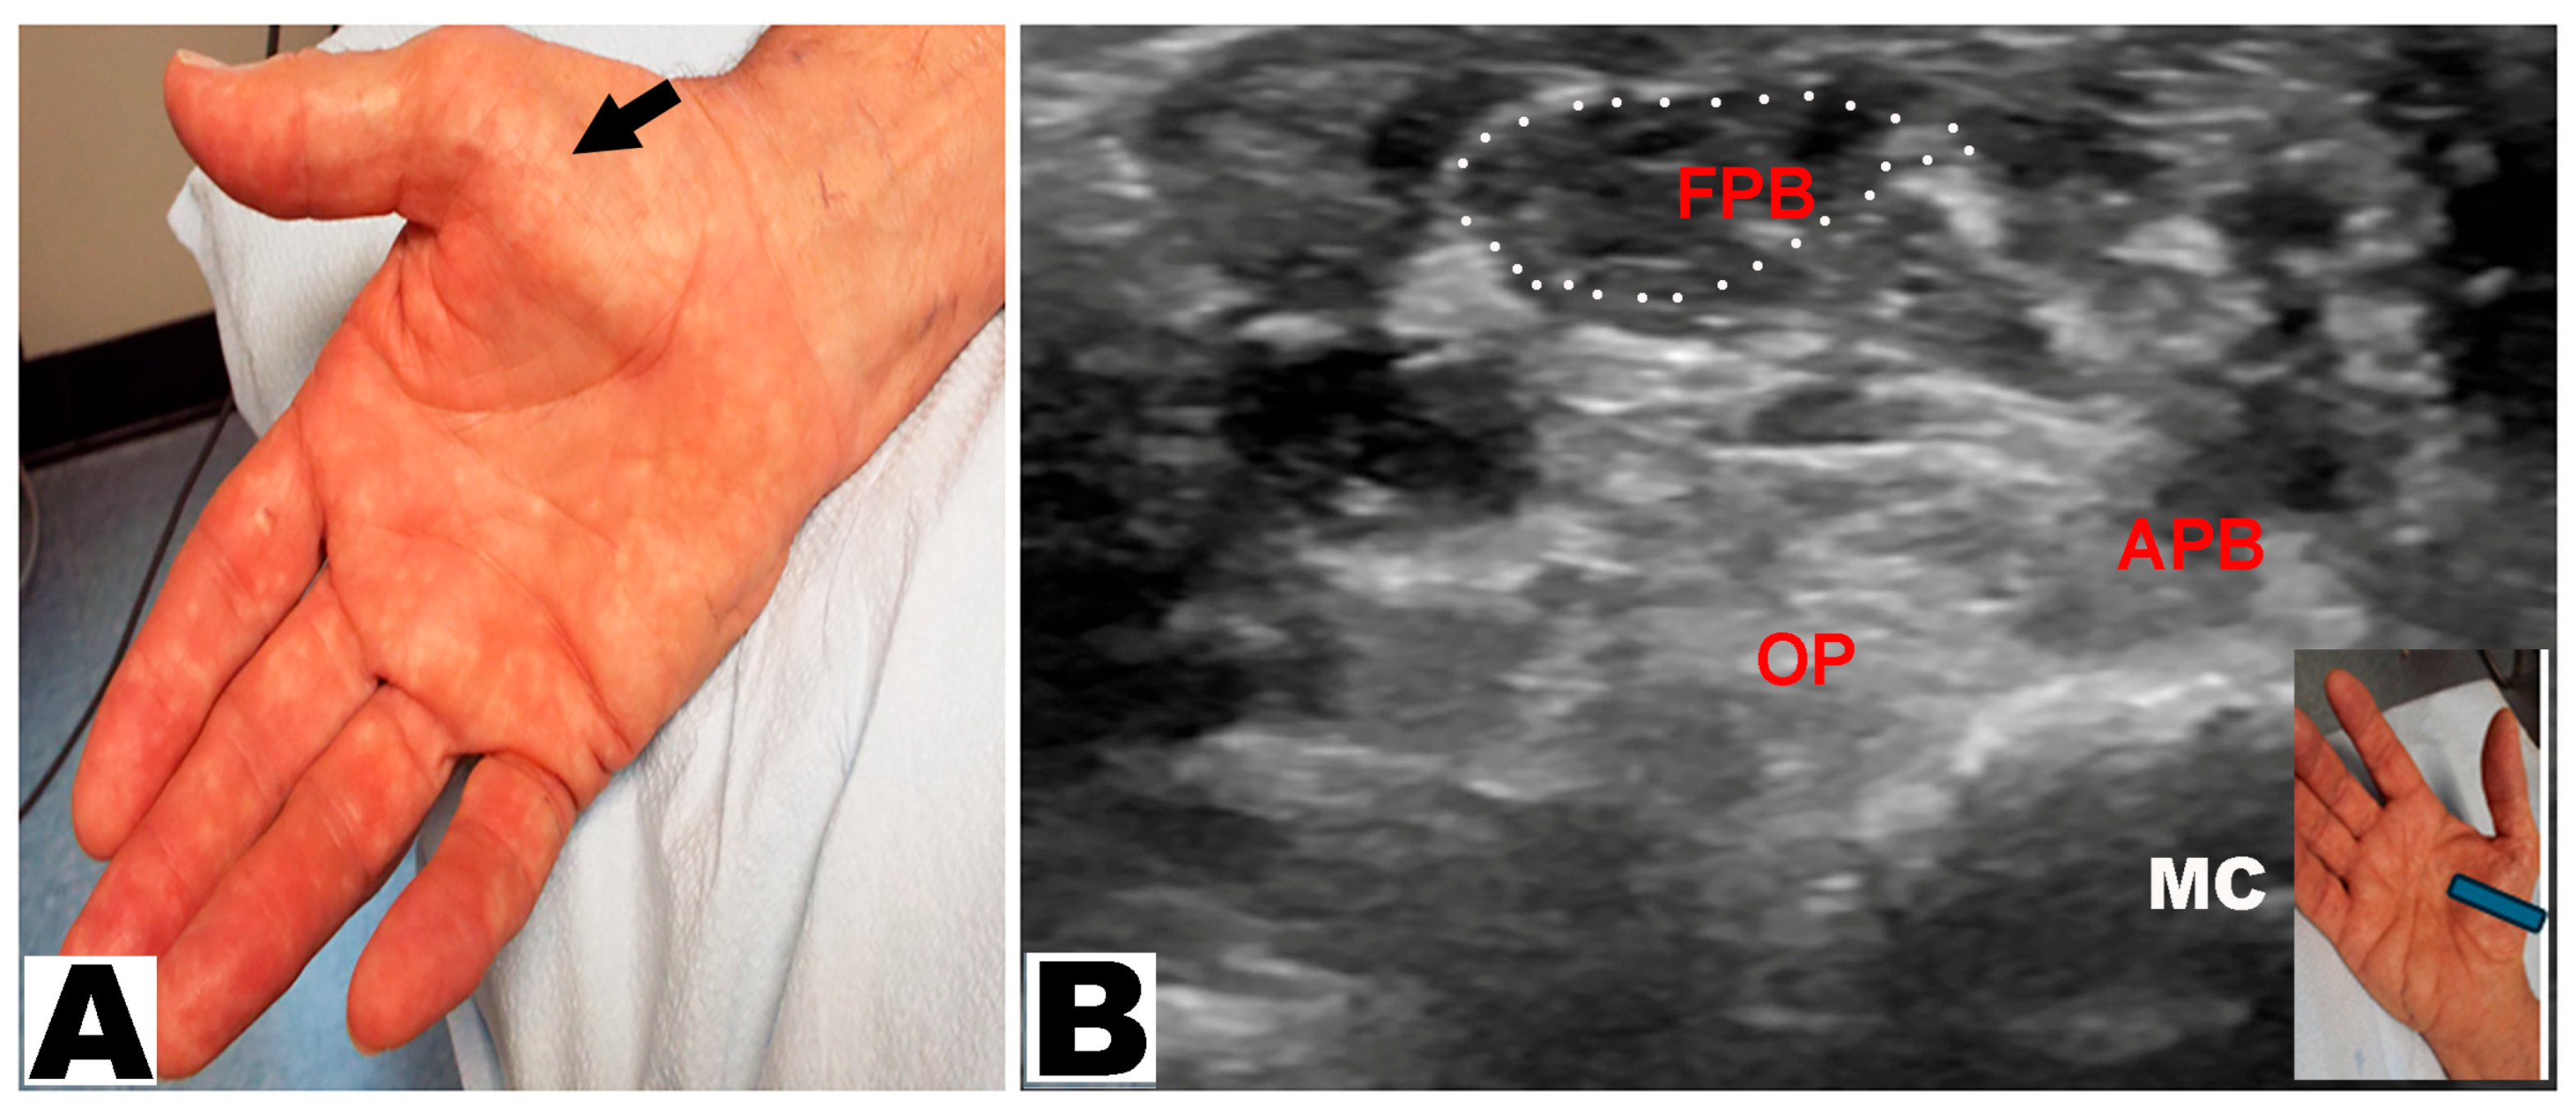

| Type of Thenar Atrophy | Description | Mechanism |

|---|---|---|

| Total | APB, OP, and FPB muscles are atrophic, leading to a “flat” thenar eminence | 1. Severe CTS: median nerve innervates all thenar muscles, including both heads of the FPB muscle |

| 2. Severe CTS and ulnar neuropathy causing atrophy of all thenar muscles, including both heads of the FPB muscle | ||

| 3. T1 radiculopathy causing atrophy of all thenar muscles, including both heads of the FPB muscle | ||

| Partial | APB and OP muscles are atrophic with an intact FPB muscle visible in the distal/medial part of the thenar eminence | 1. Severe CTS with intact deep head of the FPB (innervated by the ulnar nerve) |

| 2. Severe CTS with an intact FPB muscle due to ulnar innervation of both heads | ||

| Partial with hypertrophy of the FPB | APB and OP muscles are atrophic, causing the lateral part of thenar eminence to be flat with a prominent “bulge” on the medial aspect from a large FPB muscle | Severe CTS with an intact FPB muscle compensating for the loss of the OP muscle; more likely when the FPB muscle is entirely supplied by the ulnar nerve |